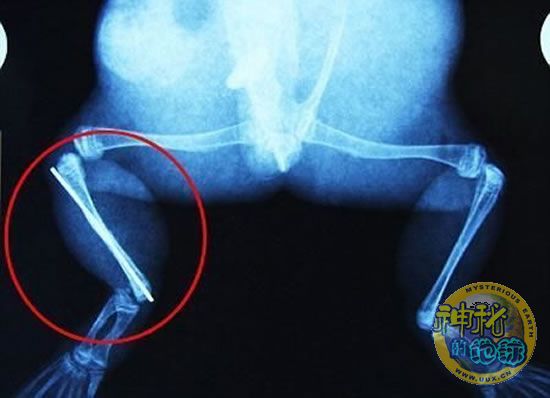

医护人员为牛蛙用钢针接上断腿

据《每日邮报》报道,上个月,南非大牛蛙布鲁莱的右小腿被邻居家的一只狗咬到,导致粉碎性骨折,现在经过2个小时的手术,它的断腿已经被接上,它也因此成为有史以来第一只通过外科手术用钢针接上断腿的青蛙。

野生生物专家安妮经常为学校写教材,她认为这是人类第一次通过手术给一只青蛙接断腿。在手术开始阶段,兽医把少量给狗用的麻醉药注入到这只青蛙体内,让它失去知觉。然后他在布鲁莱的断腿上切开一个小口,把一根小钢针植入腿里。最后兽医给它缝了9针,把切口缝合在一起。仅仅几周后,布鲁莱就能在安妮家附近活动了。这只青蛙大约已有25岁,主要以啮齿动物、蛇和其他青蛙为食。布鲁莱所属的牛蛙种群正在不断减小,目前只能在非洲南部的湿地里才能看到这种青蛙。